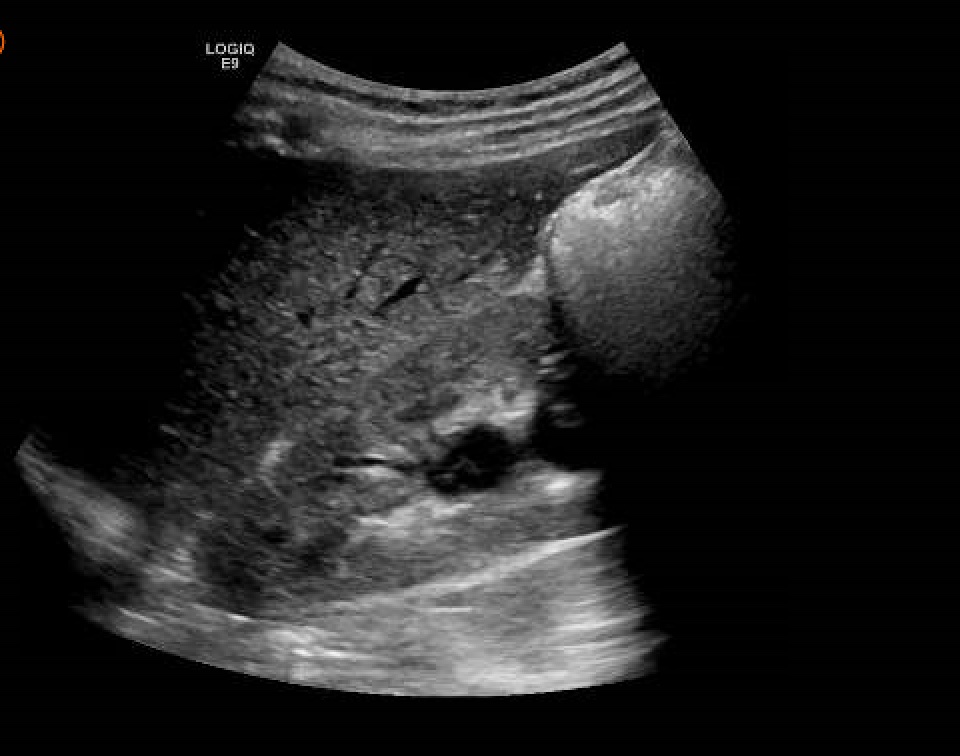

Hallazgos ecográficos

Ecografía abdomen: Dilatación moderada de ureter derecho proximal y parte de pelvis renal (14 mm) sin posibilidad de visualización de litiasis por gestación. Vejiga deplecionada. Movimientos fetales activos con latido conservado.